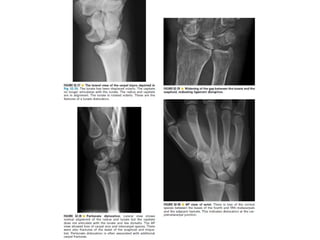

Skeletal trauma was presented by Dr Laith Fadhel with reference to Grainger's Diagnostic Radiology textbook. The presentation covered skeletal trauma as assessed through diagnostic radiology techniques. Key findings and treatments for skeletal injuries were likely discussed.